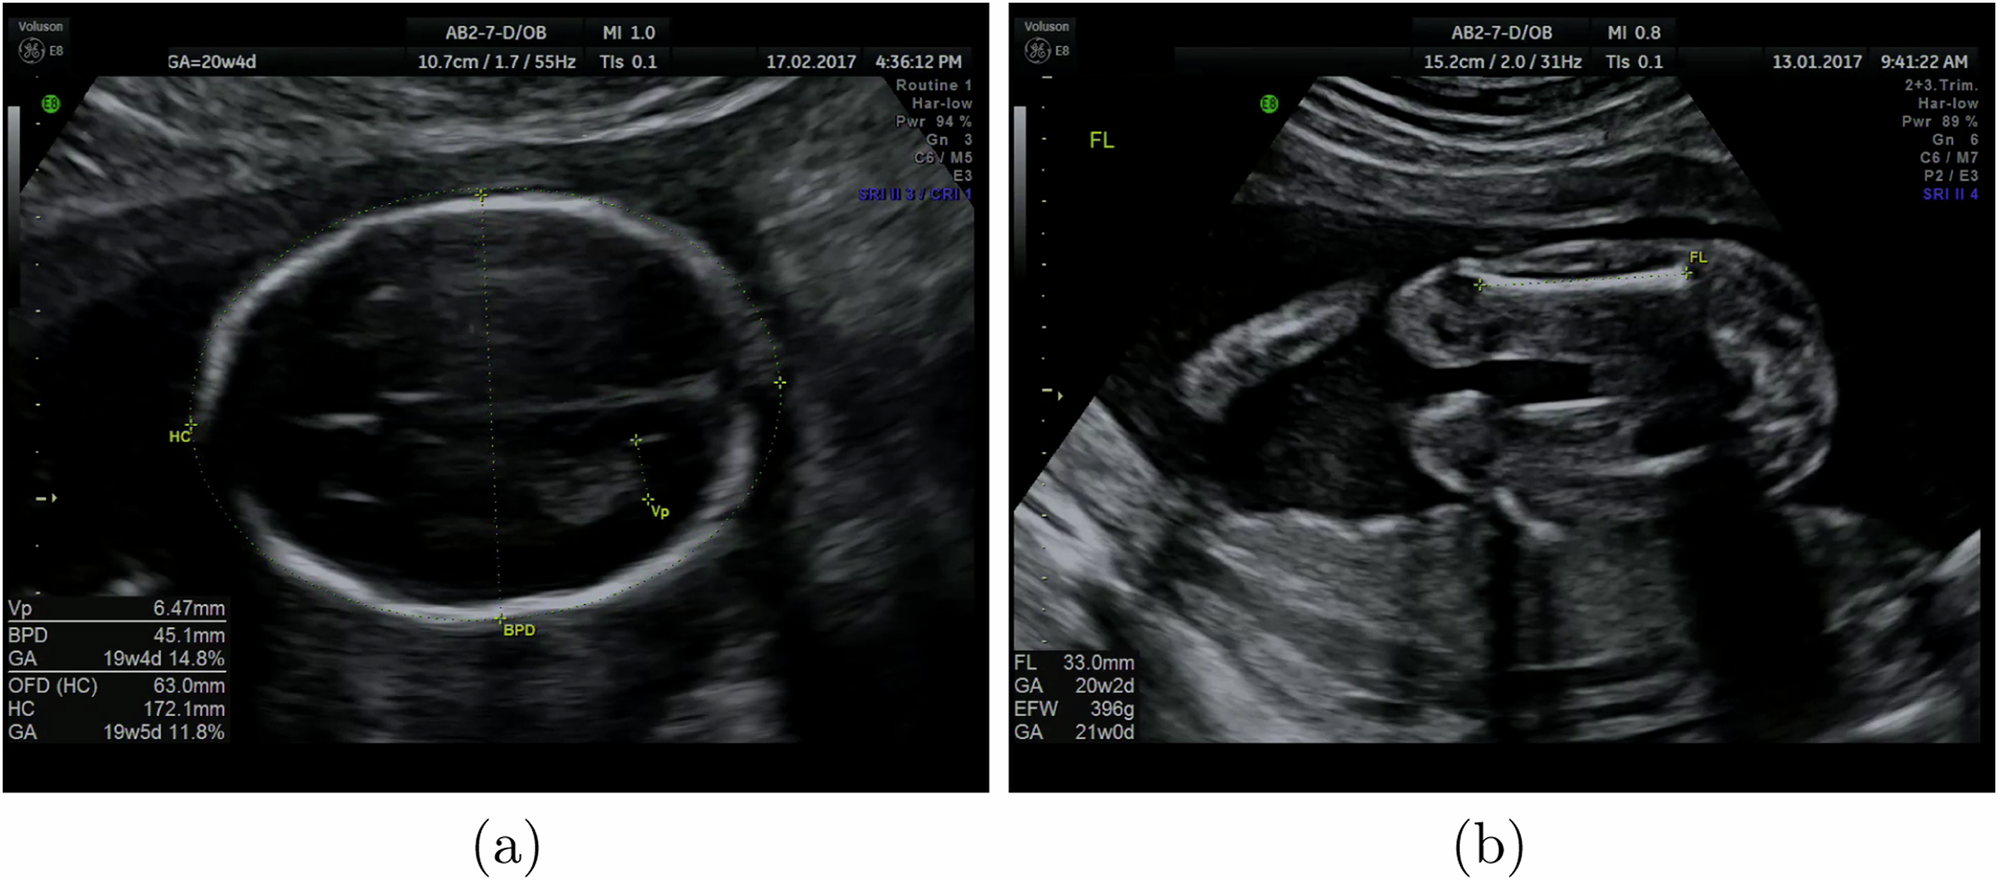

Fig. 6: Example frames from routine ultrasound examinations with a sonographer’s annotations and calipers.

Shown are a a Brain-TV image, with annotations for head circumference, biparietal diameter and posterior ventricle, b a femur image, with the femur length measured and annotated. These frames were acquired and saved by a sonographer, and we extracted their annotations to form part of our training set.